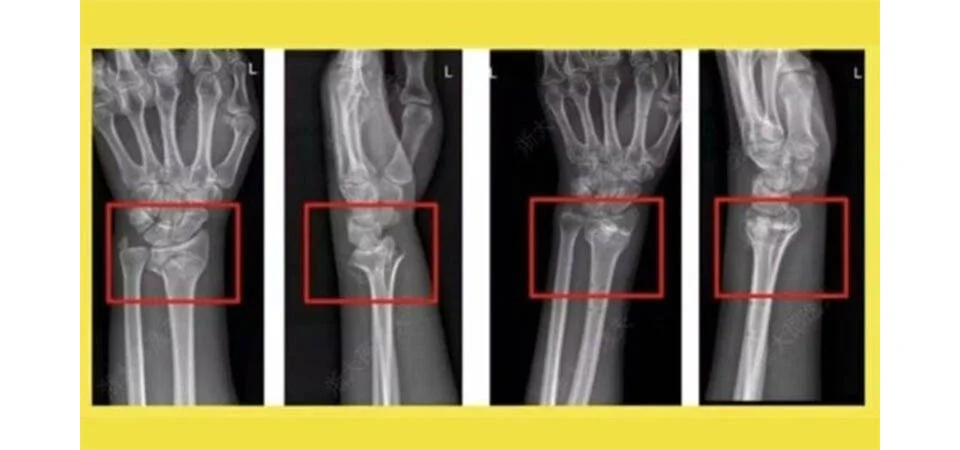

Cientistas chineses criam supercola óssea capaz de resolver fraturas em minutos

Cientistas na China fizeram um anúncio significativo este mês ao revelar o desenvolvimento de uma cola óssea inovadora, denominada Bone-02, que promete acelerar o processo de cicatrização de fraturas que, convencionalmente, exigiriam meses de recuperação. Este novo produto ortopédico foi projetado para curar lesões em minutos, segundo informações do “Global Times”. O cirurgião ortopédico Lin […]